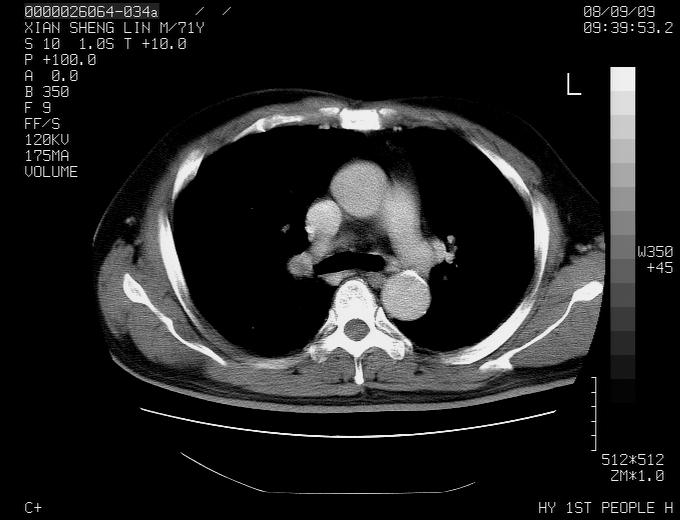

标题: CT15869:男性,71岁,因咳嗽而就诊,请讨论右上肺病变性质 [打印本页]

标题: CT15869:男性,71岁,因咳嗽而就诊,请讨论右上肺病变性质

患者,男性,71岁,因咳嗽而就诊,

典型的右肺中心性肺癌并纵隔淋巴结转移

右肺中心性肺癌并纵隔淋巴结转移可能性大!

病灶中等程度强化 还是支持肺癌诊断

考虑右肺中心性肺癌并右肺门及纵隔淋巴结转移。

1,右肺中心型ca,气管隆突旁淋巴结转移。

2,右膈明显抬高,建议肝脏扫描排除转移或原发灶。

支持右肺中心性肺癌并右肺门及纵隔淋巴结转移。